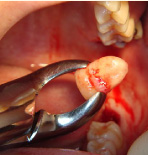

口腔外科

保存不可能な歯を抜いても親知らずがあれば、それを抜いた所に移植できるんです。

その他、難しい位置にある抜歯や歯周外科等も行っています。

- 施術前

- 施術後